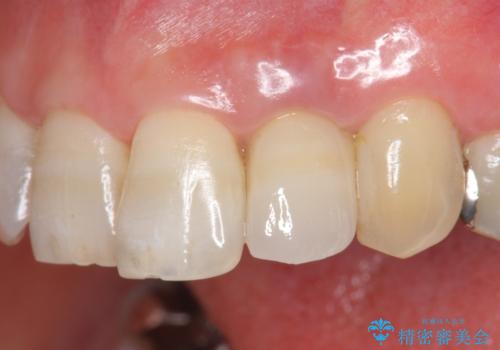

自然な色調のクラウンが製作され、審美障害が改善し喜んでいただくことができました。